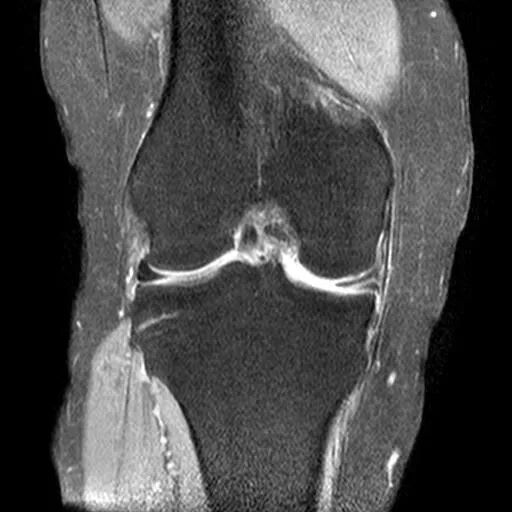

1、半月板体部的撕裂在矢状面上表现为蝶形的半月板内出现与长轴垂直的线状高信号2、前后角的放射状撕裂因与矢状面平行而表现为III级高信号3、好发于半月板的内侧1/34、外侧半月板多见

半月板放射状撕裂